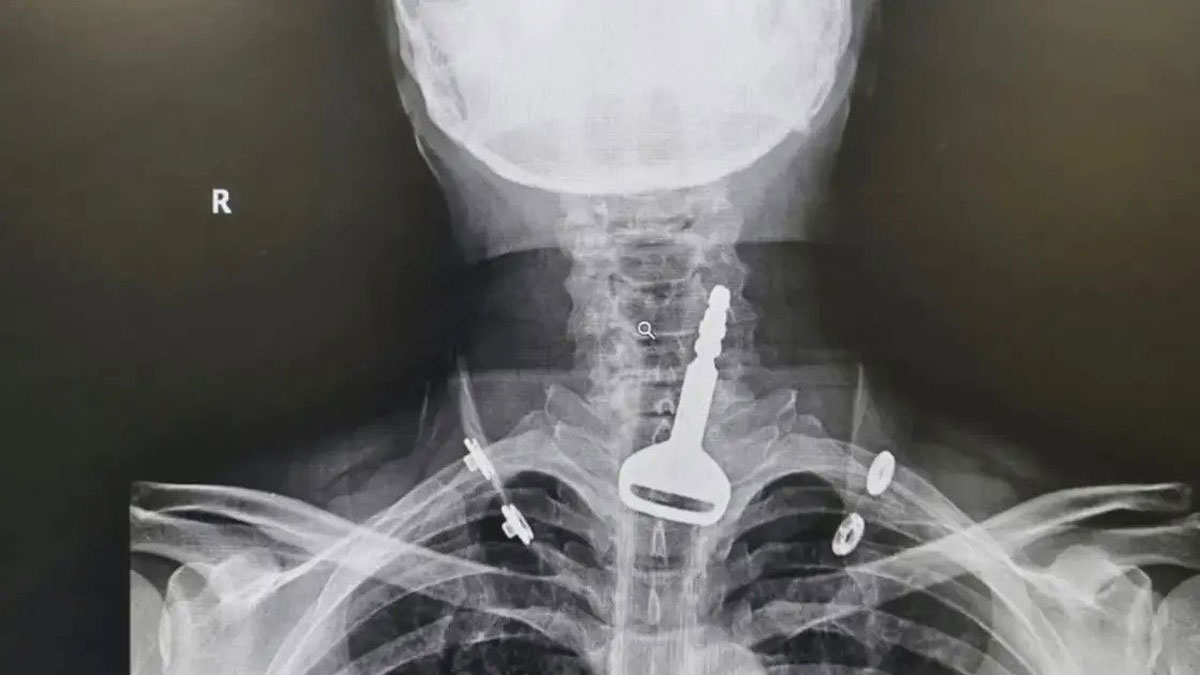

ওই ব্যক্তির গলার করা একটি এক্সরেতে দেখা যাচ্ছে, লোহার চাবিটি তার শ্বাসনালীতে আটকে আছে।

মধ্যপ্রাচ্যের সৌদি আরবে ঘটেছে এমন ঘটনা। তবে সেটি কোনো কাঁটা, চকলেট বা চুইংগাম নয়। এক ব্যক্তির গলার ভেতর আটকে গিয়েছিল গাড়ির আস্ত চাবি।

সংবাদমাধ্যম আল আরাবিয়া শুক্রবার (১৪ জুলাই) এক প্রতিবেদনে জানিয়েছে, ‘খেলার ছলে’ গলার ভেতর গাড়ির চাবি ঢুকিয়েছিলেন ৪৯ বছর বয়সী এক ব্যক্তি। সেটি তার গলার ভেতর শক্ত হয়ে আটকে যায়। পরবর্তীতে অস্ত্রোপচার করে চিকিৎসকদের সেটি বের করতে হয়।

লোহিত সাগরের আল-কুনফুদাহ হাসপাতালের একদল চিকিৎসক চাবিটি বের করত ১৫ মিনিটের অস্ত্রোপচার করেন। জরুরিভিত্তিতে তাকে ওই হাসপাতালে নিয়ে যাওয়া হয়েছিল।

পরবর্তীতে ওই ব্যক্তি স্বীকার করেন তিনি মজা করে চাবিটি গেলার চেষ্টা করেন। কিন্তু সেটি গলায় আটকে গিয়ে তার দম বন্ধ হয়ে যাওয়ার উপক্রম হয়।

গলায় চাবি আটকে যাওয়া ব্যক্তির আগে থেকেই হার্টের সমস্যা ছিল। ফলে হাসপাতালে আসার পর জরুরিভিত্তিতে অস্ত্রোপচার করা হয়। চাবিটি বের করে তাকে আবার হাসপাতাল থেকে ছেড়েও দেওয়া হয়। বর্তমানে তার অবস্থা স্থিতিশীল আছে।